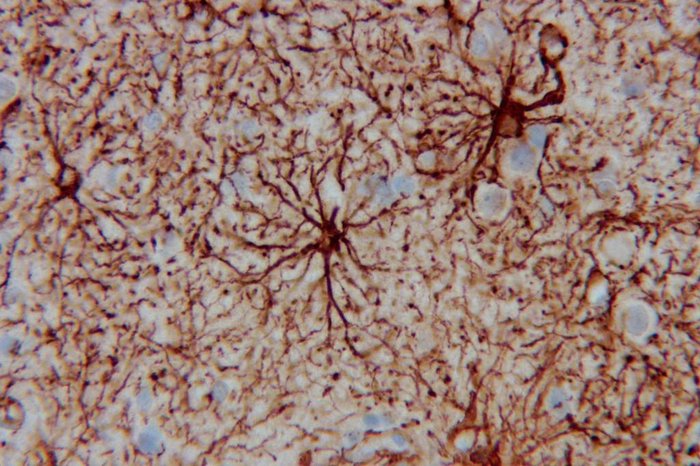

– Tivemos uma queda de 77,32% de diagnósticos de câncer. O medo de contrair a covid-19 ou de infectar parentes e amigos faz as pessoas evitarem as consultas médicas, mas as outras doenças continuam seguindo o curso natural. O tempo ideal de diagnóstico inicial de alguns tumores certamente foi perdido e ainda não temos uma dimensão das consequências – ressalta Floriano Riva Neto, especialista em patologia oncológica do CPM.

Centro de Patologia Médica (CPM)

Queda de 77,32% de diagnósticos de câncer